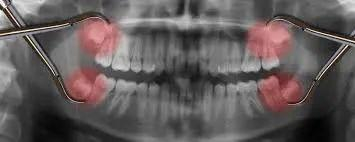

我们最熟悉的痕迹器官要数智齿和阑尾了。它们都是我们的祖先曾一度依赖素食的证明——宽大的智齿可以帮助磨碎植物纤维,而阑尾储藏着能够消化纤维的菌群。

位于牙槽最内侧的智齿总容易长歪

现代人的主食已经变得越来越精细,这两种结构的功能也发生退化,不仅帮不上忙,还时常帮倒忙——经历过智齿疼和阑尾炎的人不在少数。不过,近年有研究发现,阑尾仍储存着有益菌群,属于身体免疫大军的一份子。